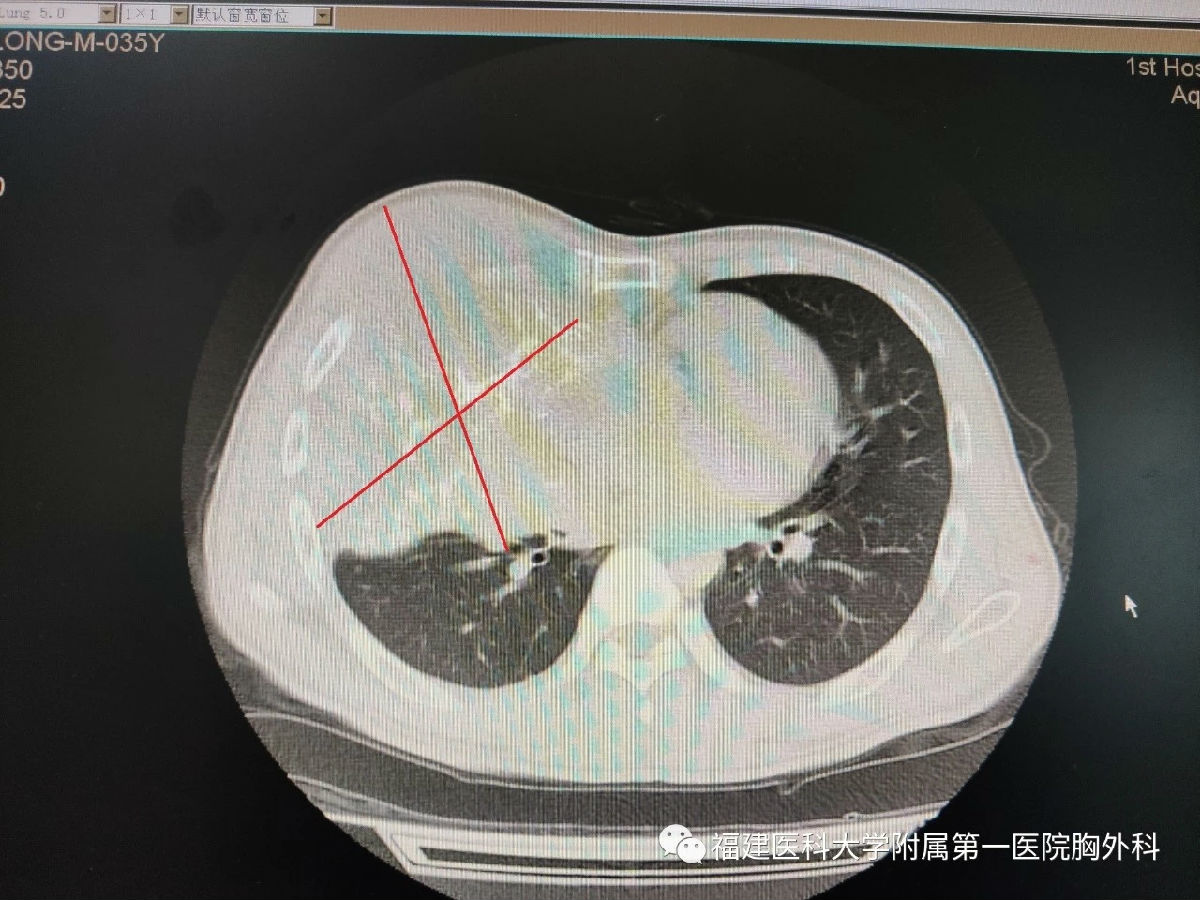

35歲的柯先生三年前發現自己的右側胸部隱隱作痛,但生活節儉的他覺得忍忍就沒事了,沒有重視,之后右胸就不斷的變大,疼痛也越發劇烈。近半年,每夜疼痛難睡,胸口像壓著石頭一般喘不過氣,也因為胸部隆起明顯走在路上更要承受異樣的目光,最終,在家人的勸說下前往當地市醫院檢查。CT報告顯示,柯先生右側胸腔內有巨大腫塊,已經侵犯到肋骨,形成巨大囊實性占位,壓迫右肺導致右肺肺不張,穿刺病理顯示為低度惡性腫瘤,治療需要將整個巨大腫塊完整的切除。但是當地醫生表示這樣巨大的腫瘤手術難度大,醫院設備和技術均沒有辦法完成這樣的手術,柯先生家人帶著他輾轉鄰市多家醫院,均是同樣的原因無法得到治療,疼痛和呼吸困難一天天加劇。

“手術風險大,而且腫瘤過于巨大,手術時會比一般的胸壁腫瘤風險更高。如果不做手術,患者右肺肺不張,疼痛難忍,他身體狀況將每況愈下,病情只會繼續加重。”邱明鏈副主任醫生介紹。

李旭主任表示,手術難度非常大,不確定因素太多了,患者腫瘤體積巨大,血管分布復雜且豐富,瘤體侵犯包繞肋骨,切除過程中腫瘤暴露困難,需要將右側胸壁四根肋骨和肋間肌一并切除,但這會造成較大的胸壁缺損。為了克服胸壁腫瘤完全切除和胸壁重建這兩大難題,李旭、邱明鏈團隊經過反復的討論溝通,最終確定了手術方案。